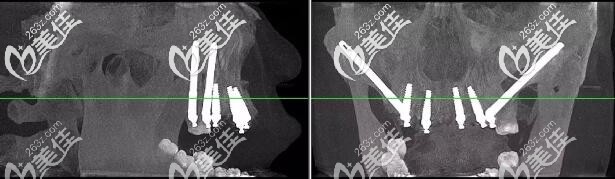

术后肖先生CBCT口腔影像